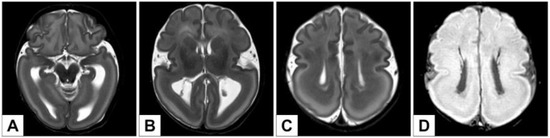

3.2. Neuroradiological Imaging